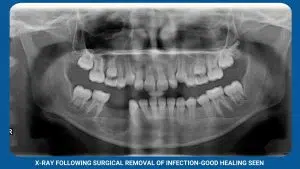

Sometimes, lesions go beyond diagnosis and require removal. Simple cysts, bumps, and infections? This is where lesion removal steps in, eliminating the troublesome tissue and promoting oral health.